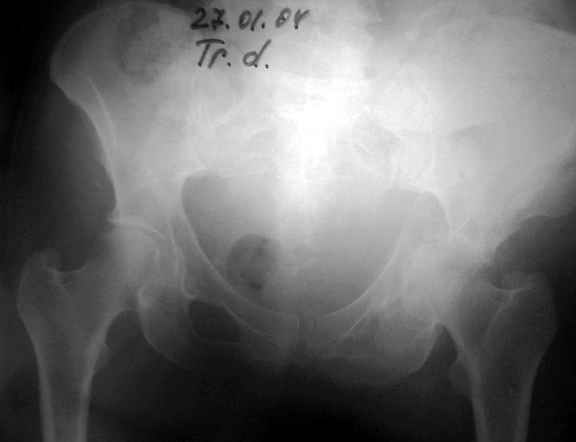

Женя! Класный перелом. Отлично репонируется изнутри таза, но лучше фиксированть сзади. Классический перелом для двустороннего доступа.

Однако есть альтернатива. Репозиция из подвздошного доступа тазовыми щипцами с разнодлинными браншами или тазовым пистолетом, а фиксация задней колонны через седалищный бугор или тазрвыми винтами 4,5 или каннюлированными 6,5 или 7,3. По-моему я посылал на ортофорум такой снимок, когда жаловался на ишемический неврит седалищного нерва через сутки после операции. Не забудь про шейку бедра - мне кажется будет хорош длинный PFN любой фирмы, какую ты найдешь, а нет так UFN + miss a nail, как это здорово делают мои земляки - Ебурбуки. Пока.

27.01.04

Anatoly F Lazarev 03 Сентябрь 2004, 22:39

Высылаю пример еще одного случая, остеосинтез пластиной из подвздошного доступа.